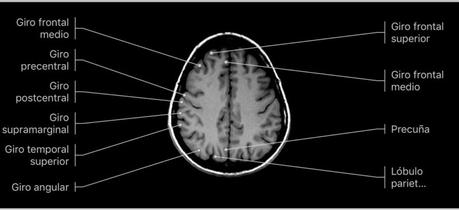

Giros frontales